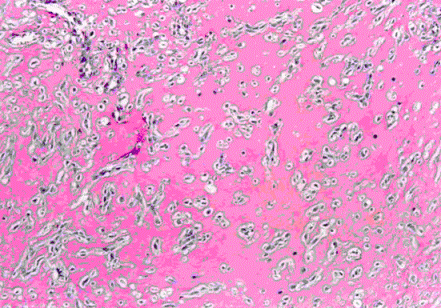

65、多项选择题

患者女,35岁,多年月经不调,原发不孕,促排卵治疗6个月余,无效。B型超声:内膜增厚,回声杂乱。刮宫内膜组织中量,灰白,质地软脆。光镜下组织图像如图所示。

该图像提示()。(提示因患者年轻、未生育,本人有强烈意愿保留生育功能,充分评估后给予大剂量孕激素连续治疗3个月,再次刮宫组织图像如下图所示。)